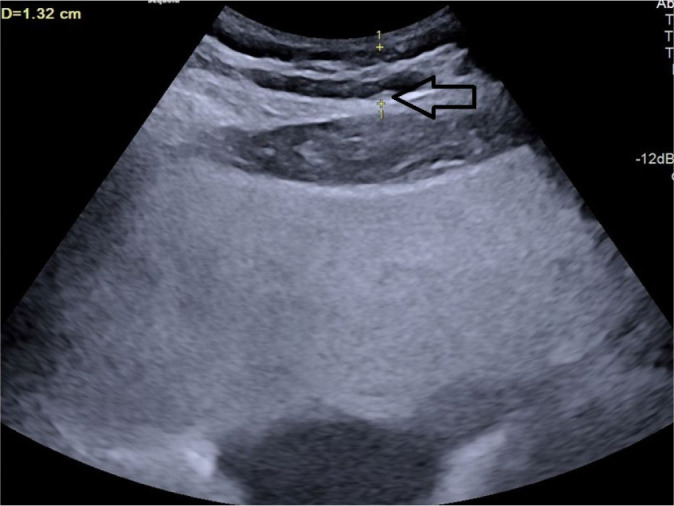

Aim: Abdominal obesity is recognized as the best predictor of cardiovascular disease risk. While body mass index has traditionally been used to measure obesity, recent evidence suggests that visceral adipose tissue may be a better indicator of cardiovascular disease risk. Various surrogate imaging markers of visceral adipose tissue have recently been described, such as posterior right perinephric fat thickness, preperitoneal fat thickness, and the abdominal wall fat index. This study aimed to examine the link between atherosclerosis through measurement of carotid intima-media thickness and markers of abdominal obesity using ultrasonography.

Material and methods: This was a hospital-based prospective observational study. Patients with a body mass index of 25-40 were included as cases and those with a body mass index 18.0-24.9 as controls. Posterior right perinephric fat thickness, preperitoneal fat thickness, and abdominal wall fat index were measured and compared with carotid intima-media thickness in cases.

Results: A total of 100 cases and 100 age- and sex-matched controls were included. Body mass index did not show any statistically significant correlations with carotid intima-media thickness in this study. Among the visceral adiposity markers, posterior right perinephric fat thickness was the most sensitive and specific predictor of carotid intima-media thickness, while the abdominal wall fat index was the least sensitive and specific.

Conclusions: Ultrasonographic markers of visceral adipose tissue, especially posterior right perinephric fat thickness and preperitoneal fat thickness, demonstrate a stronger association with carotid atherosclerosis than body mass index, making them useful predictors, particularly in individuals with high body mass index. These markers can be measured during routine abdominal ultrasounds to screen for atherosclerosis risk in patients with abdominal obesity.